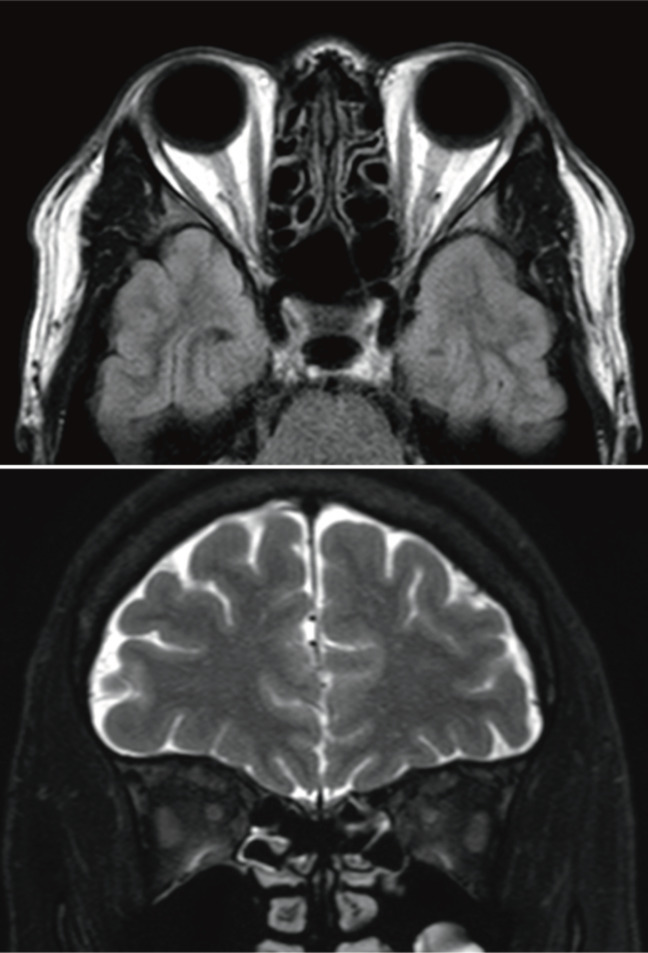

Results: A 52-year-old man had a sudden loss of vision in the left eye. Examinations revealed the presence of a serum monoclonal immunoglobulin (IgM kappa) in the serum. Even after a session of steroid pulse therapy, optic neuropathy became bilateral and then resolved almost completely after 4 months. The condition progressed to WM with multiorgan lesions years later. There was no evidence of optic neuropathy recurrence. The literature revealed two cases of monoclonal gammopathy (MG): a 64-year-old man with multiple myeloma (MM) with IgA lambda and a 51-year-old man with MM with IgG kappa. These cases have similar conditions: 1) visual reduction as an initial symptom of MG, 2) bilateral involvement, 3) no sign of central nervous system (CNS) infiltration shown by normal brain magnetic resonance images, and 4) recovery to a visual acuity of ≥1.0 bilaterally with no reoccurrence. The excessive Igs or B-cell hyperactivity may activate an autoimmune mechanism that reversibly interferes with the bilateral optic nerves.